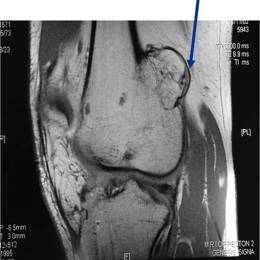

Radiographic imaging is used to help form a diagnosis. These include X-Ray, MRI, CT and Bone Scans.

An example of an Osteochondroma MRI is shown.